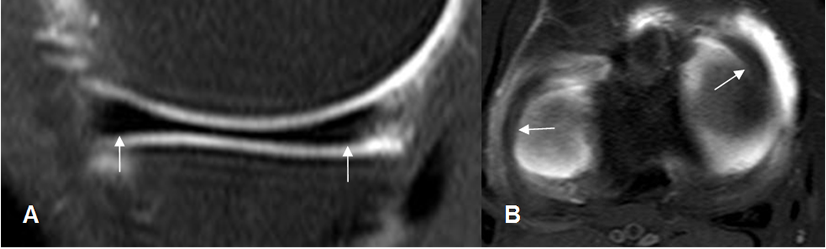

El LCP también se aprecia como una banda hipointensa en todas las secuencias. (2). (Fig 17). El ángulo entre los ejes de la inserción tibial y femoral, normalmente mide 123º. (11).

Este ligamento está rodeado por los ligamentos meniscofemorales que se originan del cóndilo femoral interno y se insertan en el menisco externo. Son el anterior o de Humphrey y el posterior o de Wrisberg. Estas estructuras no deben confundirse con cuerpos libres intra-articulares. (2). (Fig 18 y 19).

Fig 17. LCP normal.

A: RM sagital en T1 y B: RM sagital en T2. Ligamento normal, hipointenso en todas las secuencias.

Fig 18. Ligamentos meniscofemorales.

A y B: RM sagital en T1. Ligamento meniscofemoral anterior (Flecha delgada) y posterior (Flecha gruesa).

Fig 19. Ligamentos meniscofemorales normales.

A: RM coronal en T1 y B: RM coronal en STIR. Ligamento menisco femoral posterior (Flecha delgada), en relación con el LCP (Flecha gruesa). Menisco externo (Punta de flecha).